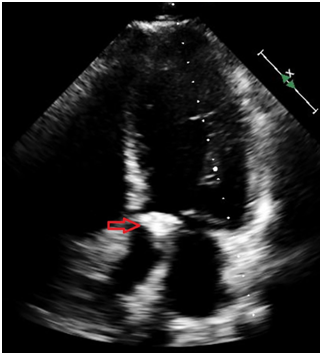

A 31-year-old Caucasian man presented to the hospital with 4day-history of left upper quadrant abdominal pain and left sided pleurisy. He had recently failed therapy for chronic HCV mono-infection, genotype 1a, with fibrosis score of F0. He admits to using intravenous recreational drugs. Vital signs were normal except for heart rate of 130/min. The abdomen was tender in the left upper abdominal quadrant with no of peritoneal irritation. Initial blood investigations revealed leukocytosis of 21.3x103/µl with normal renal function and liver enzymes. Computed tomography of the abdomen with IV contrast showed a large splenic infarct (Figure 1). He had no recent abdominal trauma or abdominal surgery. Streptococcus constellatus was cultivated from two sets of blood cultures on day three. Comprehensive workup excluded mononucleosis, pancreatic disorders, HIV, autoimmune/collagen vascular disease, sickle hemoglobinopathies, malignant hematologic disorders (normal peripheral blood smear, SPEP and flow cytometry), hepercoagulable state (normal protein C or protein S; normal lupus anticoagulant, factor V, prothrombin). Patient had no signs of ARDS, sepsis, septic shock or toxic shock syndrome. Patient no recent cardiac catheterization (angiographic embolization), sclerotherapy of esophageal varices, abdominal surgery (pancreatectomy, or liver transplant), vasopressin infusion, or embolization for splenic hemorrhage. Echocardiogram showed the presence of 2.5x1.5cm2 vegetation of the aortic valve with perforation, severe regurgitation and aortic root abscess (Figure 2). Magnetic resonance imaging (MRI) of the brain showed numerous brain abscesses, without mass effect or midline shift. This case was complex and Duke’s criteria were used to make the diagnosis of IE. The patient received aortic valve replacement and his post-operative course was uneventful. Administration of ertapenem was continued for 8 weeks. The patient had full neurological recovery and repeat MRI of the brain showed complete resolution of the abscesses. Follow-up echocardiogram showed no thrombosis or vegetation of the bioprosthetic valve.

Figure 1A) Computed tomography of the abdomen.

Figure 1B